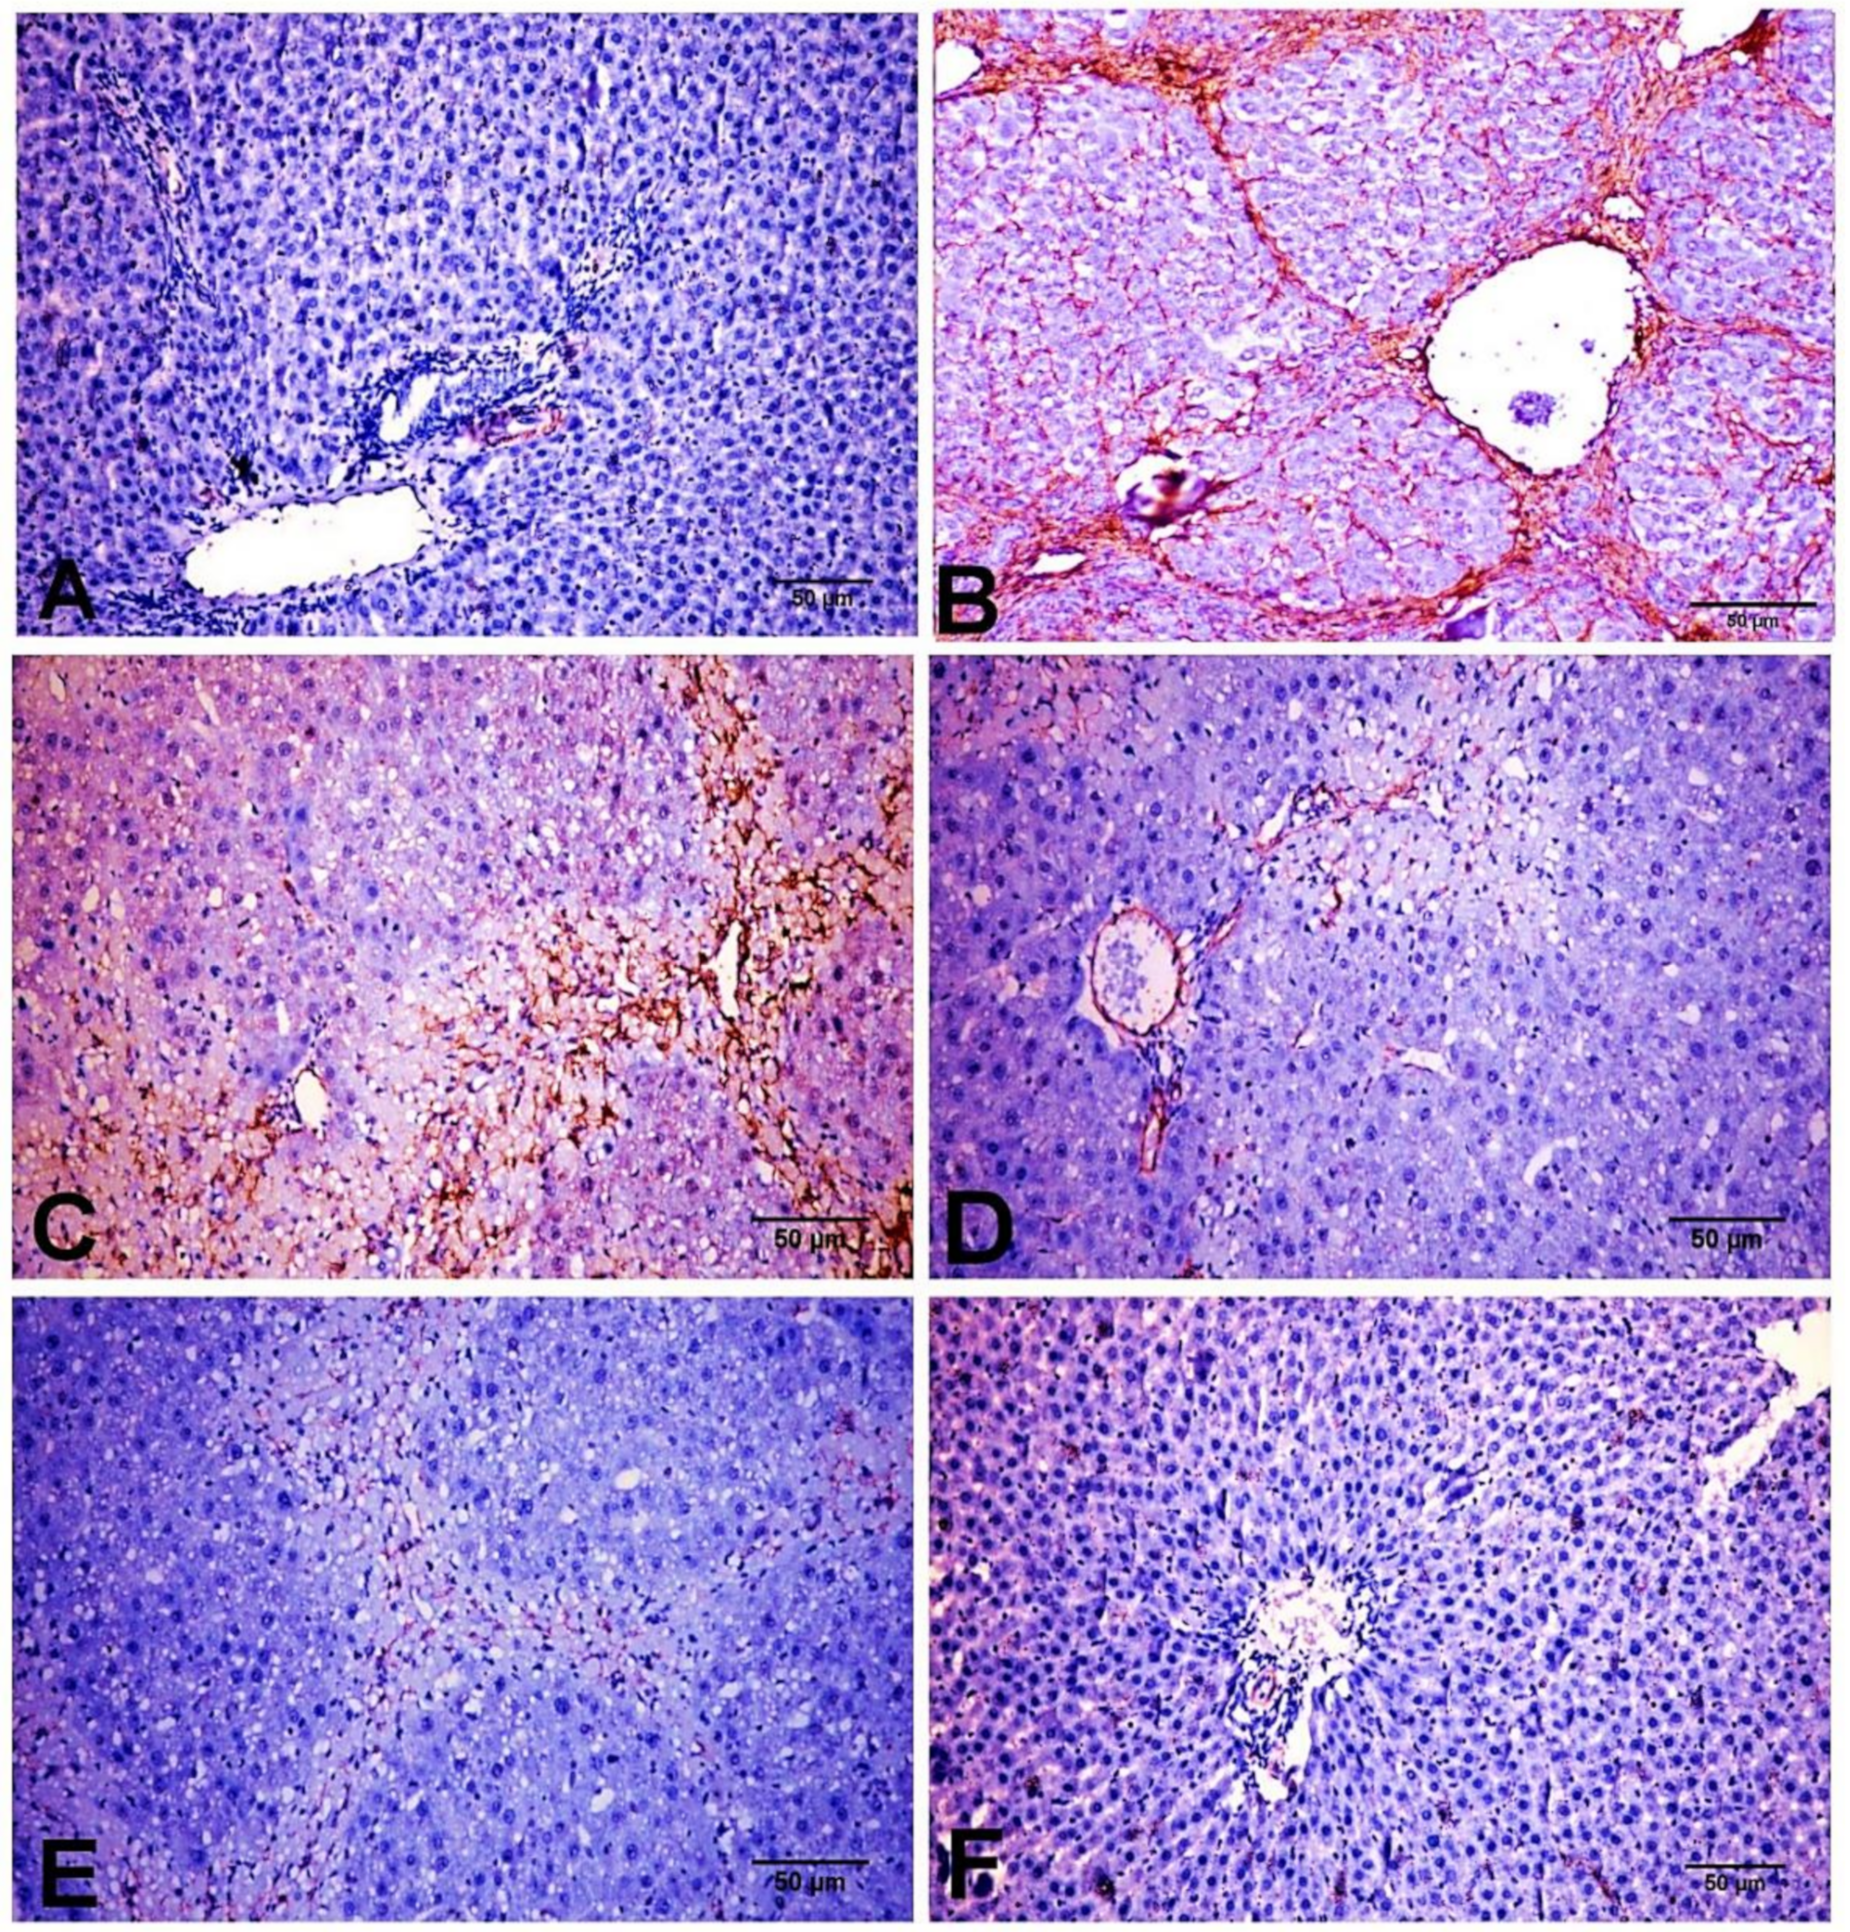

2.6. Effect of D-Carvone on Hepatic α-SMA, TGF-β1, and SMAD3 Protein Expression

4.7. Immunohistochemical Assessment